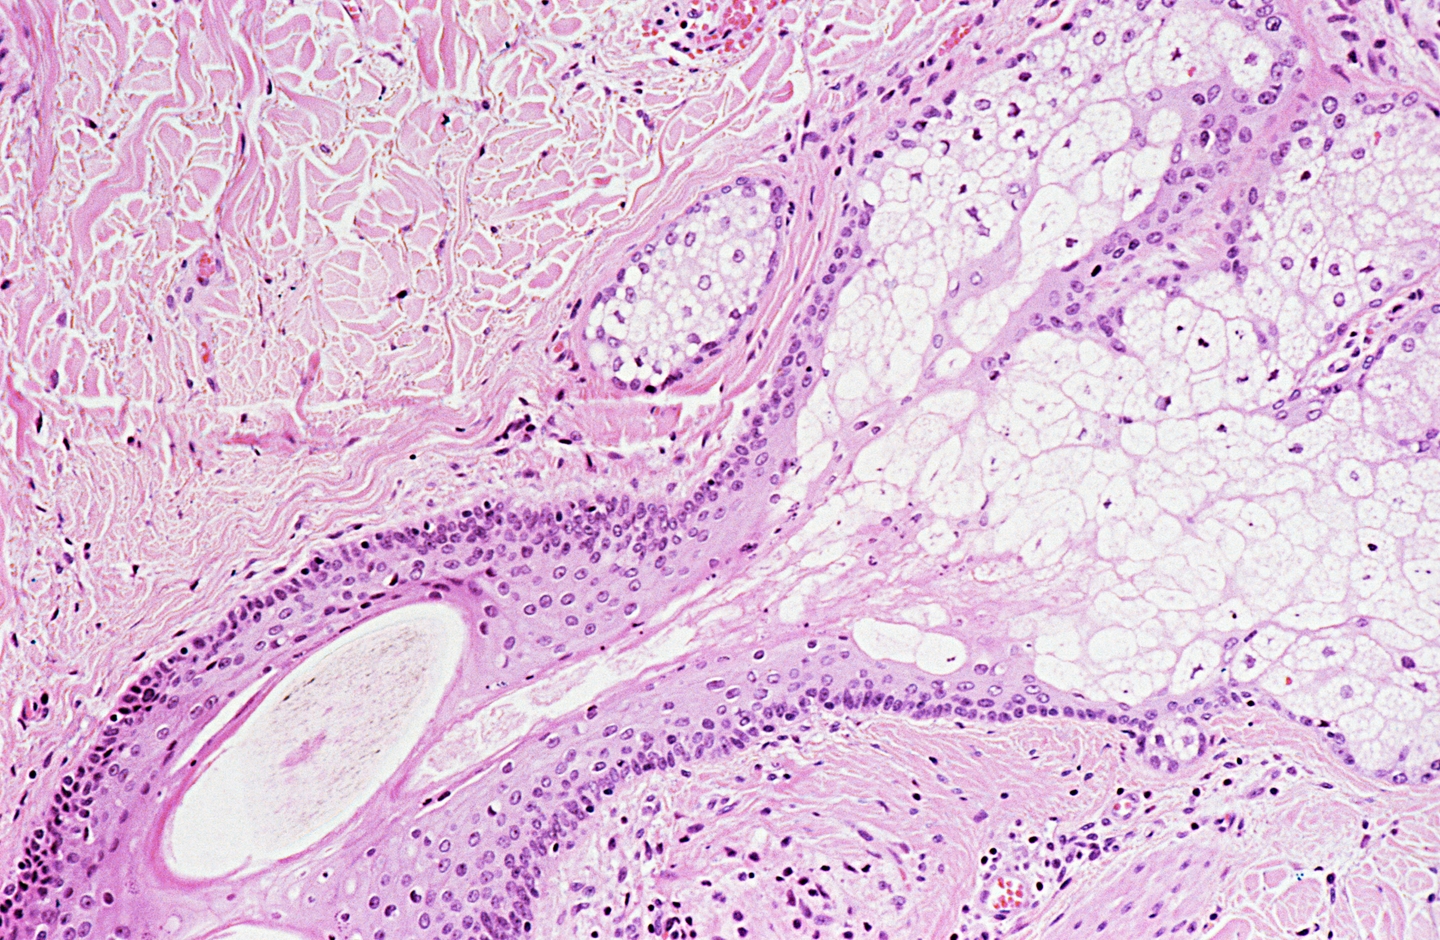

The skin cells

The skin cells 112 фотографий